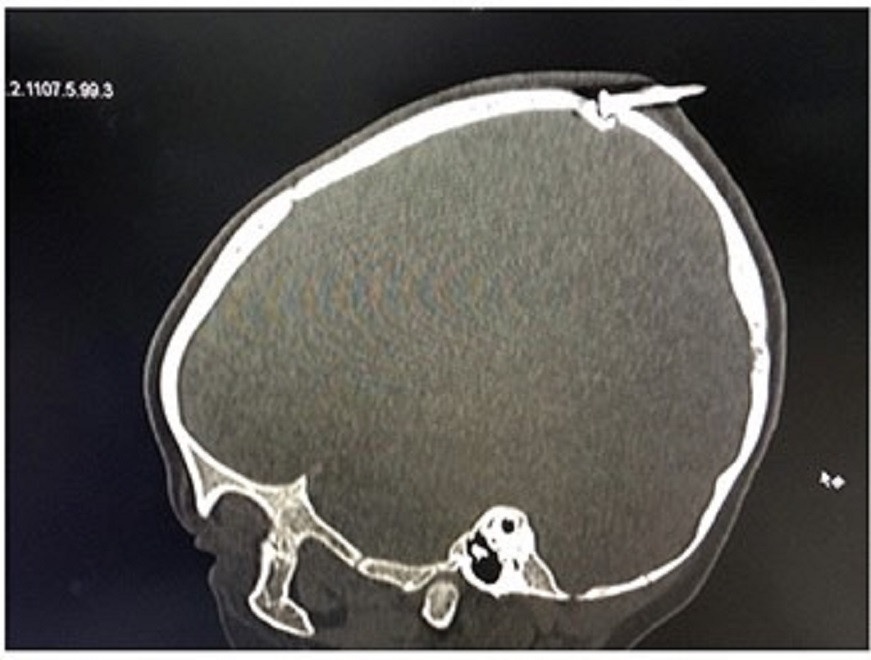

Các bác sĩ nhận định, cây đinh dài khoảng 3 cm găm qua xương sọ của bé, có nguy cơ làm rách màng cứng, gây tổn thương não, cần phải phẫu thuật để xử lý sớm.

Chiếc đinh dài khoảng 3 cm đâm xuyên xương sọ của bé. Ảnh: BVCC.

Bác sĩ chuyên khoa I Nguyễn Văn Toàn, khoa Chấn thương chỉnh hình - Bỏng, cho biết rất may, cây đinh chưa làm rách hoàn toàn màng cứng sọ não. Nếu không tiến hành phẫu thuật kịp thời, nguy cơ nhiễm trùng não rất cao và còn ảnh hưởng đến sự phát triển não của bé sau này.